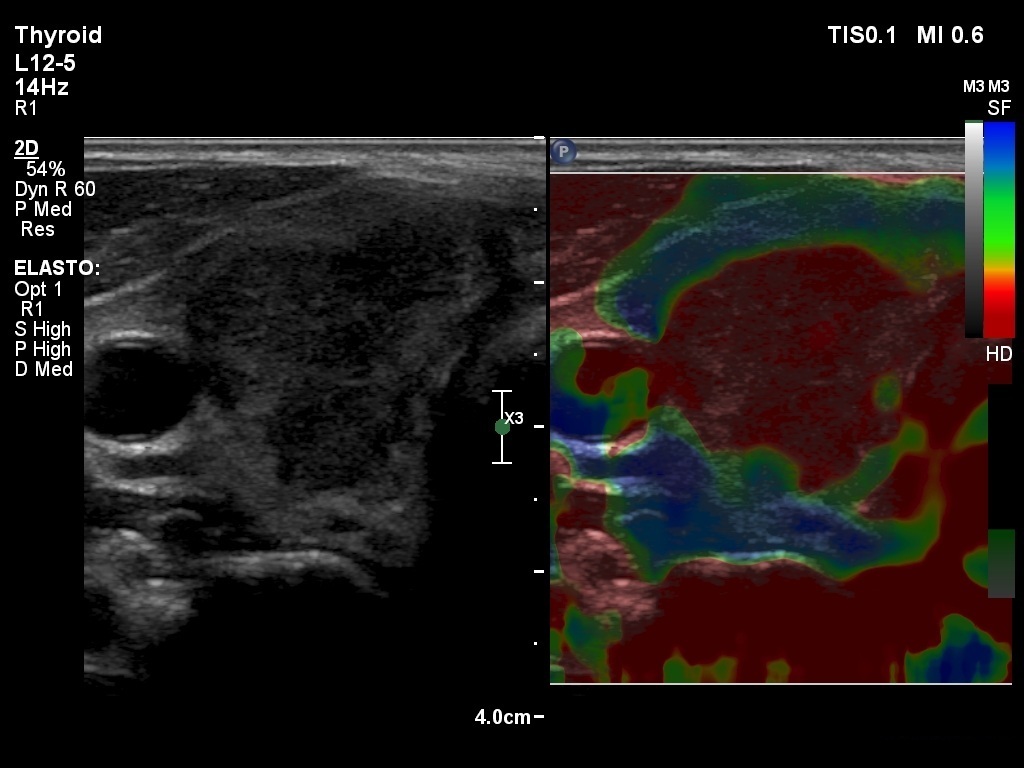

First examination (1st to 3rd rows of images):

Ultrasonography: Both lobes presented hypoechogenic ill-defined areas. The echogenicity index was 80% in the right lobe while 20% in the left thyroid. The vascularization was significantly decreased.

Elastography demonstrated hard areas according to the hypoechogenic field in the left lobe while almost the entire right lobe proved to be hard.Cytological diagnosis: subacute, granulomatous de Quervain's thyroiditis.